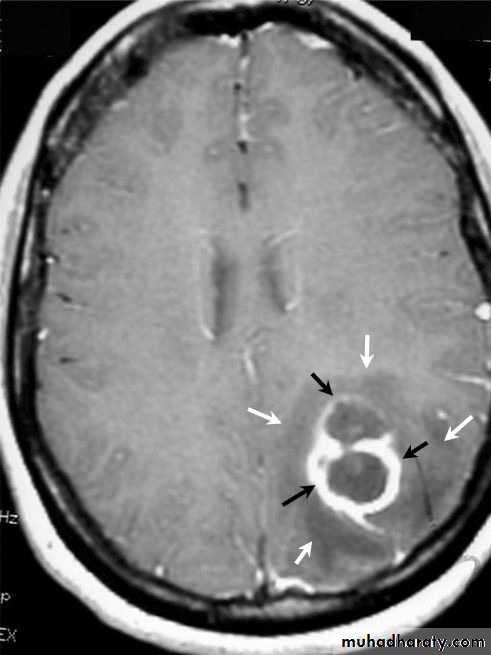

Brain Abscess MRI

• MRI is done with gadolinium enhancement.

• They will show a single (or multiple) space occupying lesion that is well delineated with an enhancing wall, with variable surrounding oedema.